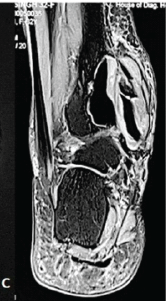

Surgical Treatment of Anchor-induced Heel Pain after Minimally Invasive Repair of Acute Achilles Tendon Rupture Using Percutaneous Achilles Repair System Achilles Midsubstance SpeedBridge™ Repair: A Case Report

David Roche , Teodor Negru , Julien Paquot , Ronny Lopes ………………………………p.122-126